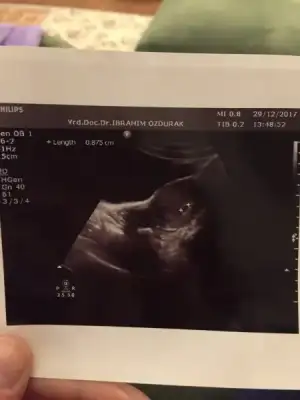

Yükleyebildim mi bilmiyorum ultrason görüntüsünü ilk kontrolüme bugün gittim. Nihayet gidebildim:) Keseyi gördüm kalp atışlarıda görülüyor dedi doktor ama dinletmedi. Ultrasondan oldum olası bişey anlamam.doktordan geldiğimden beri kağıtla bakışıp duruyorum:anneadayı::KK200:

Ben bebeği görüyorummmm. Ay miniklerimiz yaaa insan tuhaf oluyor :)